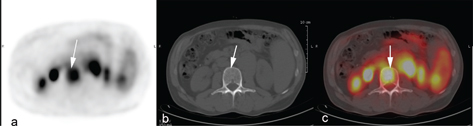

No randomized studies have been performed comparing the outcomes of patients where treatment selections occurred with or without the information provided by PET/CT. In the pre-PET/CT era, bone marrow involvement rate in HL was considered relatively rare compared to rates reported in non-Hodgkin lymphoma. The widespread use of PET/CT has changed this perception and bone marrow involvement represented by focal FDG-avid lesions on PET/CT is observed in around 20% of the patients, a four-fold increase compared to the 5% typically reported when assessing only with bone marrow biopsies (Figure 1). Very few patients will have bone marrow involvement in the setting of a positive bone marrow biopsy and negative PET/CT, and clinically relevant upstaging, as a result of bone marrow involvement by biopsy alone, is exceedingly rare (14, 15). Therefore, the need for invasive staging in HL has been completely abandoned and PET/CT is the only disease staging procedure necessary prior to therapy. The fact that focal FDG-avid bone marrow lesions are reported to be associated with worse outcomes suggest that the additional findings by PET/CT add relevant prognostic information (16, 17). With a first peak in HL incidence around the age of 15–34 years, the large proportion of young patients that are exposed to ionizing radiation is a greater concern than in most other malignancies that occur in older age groups (18). Using a contrast enhanced CT leads to 3 times higher radiation exposure as using a low-dose CT, but using contrast enhanced CT component in PET/CTs rarely changes disease stage or management strategy in lymphoma (1921). Therefore, a contrast-enhanced CT component can be reserved to patients where the added diagnostic value is needed for other medical reasons (7). Another important aspect of contrast-enhanced CT component, in particular in the treatment response assessment setting, is that contrast fluids lead to stronger SUV increase in the liver and mediastinal blood pool as compared to lymphoma tissue (22). As the visual liver to lesion FDG uptake ratio is now the standard way of assessing metabolic response in tumors, this change may have important clinical consequences.

Fig 1

Figure 1. An HL patient with focal lesions in the bone marrow that are not visible of CT. This is one of the most frequent reasons for PET-ascertained upstaging to stage IV disease.